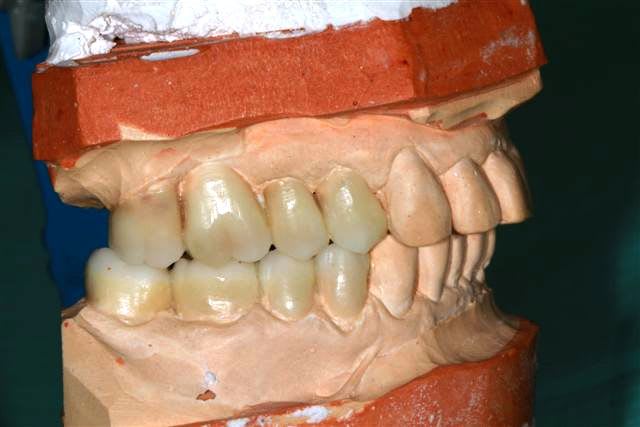

début du Waxup.

Pour les incisives du bas, je pense diminuer le bord libre.

reste à tailler le bloc antérieur.

Les wax up sont très beaux ! j'aimerais bien que mon prothésiste me fasse des wax up bicolore comme ça...

secteur gauche on a une classe 2 d'Angle molaire : donc dans l'idéal la cuspide de 25 devrait légèrement être mésialée.

Et la cuspide distale de 26 légèrement plus petite pour respecter la courbe de spee.

Merci pour les waxups, j'ai fait la mise en place et Brigitte la finition.

Pour 25/26 c'est exact et la cuspide distale de 47 remonte trop...

pardon pxav , mais tes waxups , ça va pas du tout !

il faut vestibuler le haut considerablement et meme un peu le bas .tout est verouillé pire qu'avant .il faudrait sortir les cuspides vest d'au moins 2 mm minimum .donner un peu d'air en decalage lateral immediat .

je n'ai pas l'impression que les modeles soient en centrée .